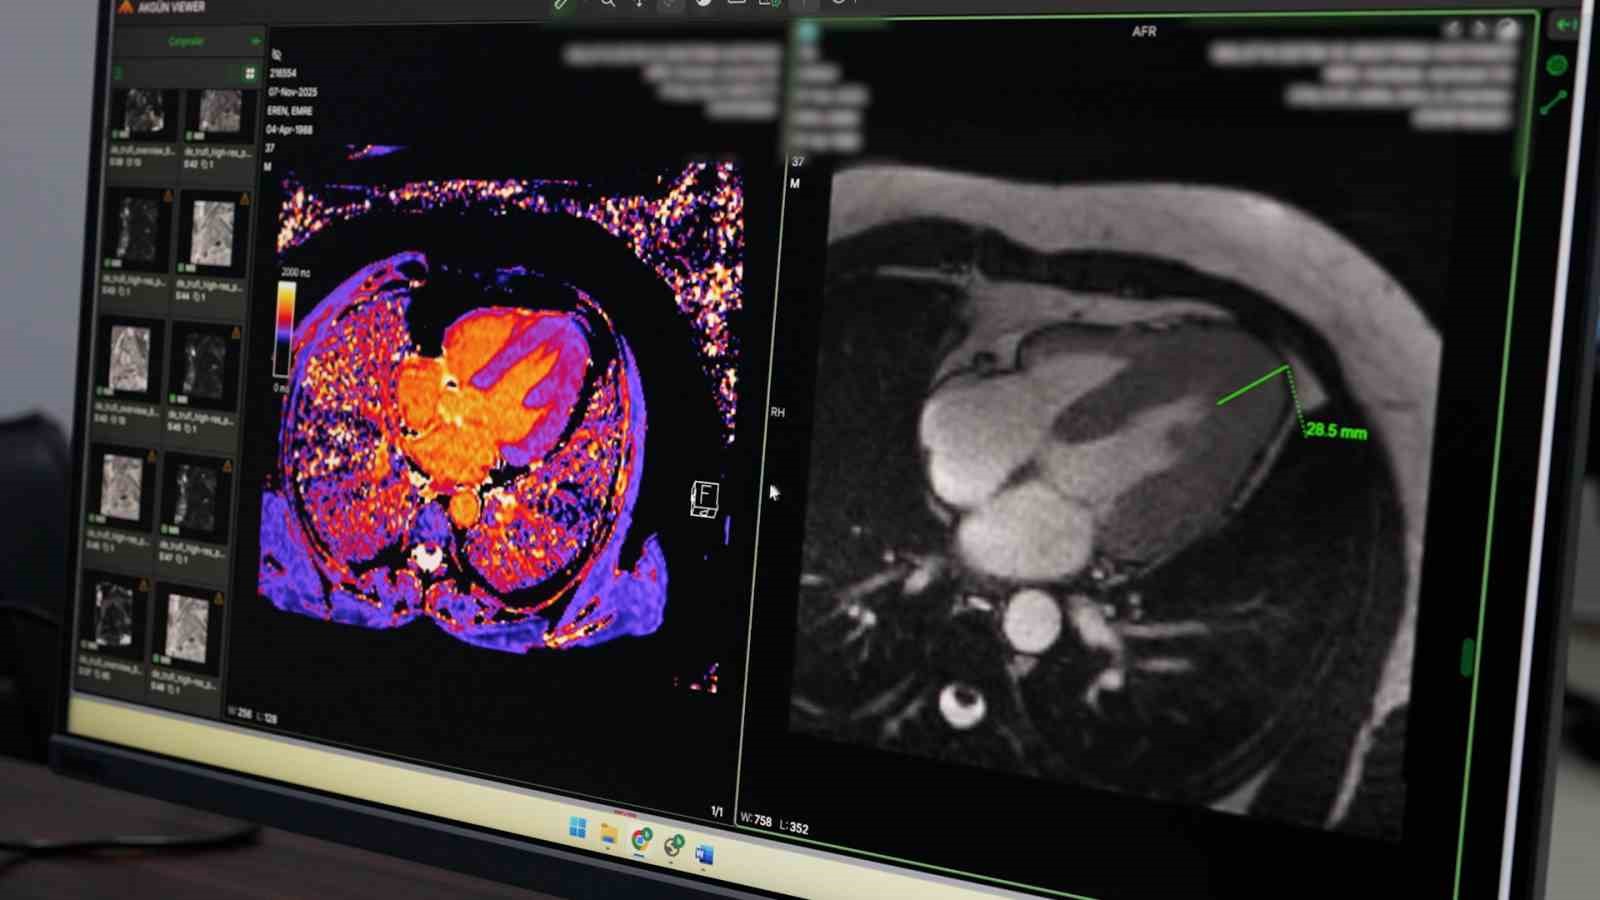

Hastanede uygulanan koroner BT anjiyografi yöntemiyle kalp damarlarının girişimsel işleme gerek kalmadan görüntülenebildiğini belirten Petik, bu sayede hastaların klasik anjiyografi öncesinde detaylı şekilde değerlendirilebildiğini ifade etti. Yeni başlatılan kardiyak MR uygulamasının da kalp kası ve kapak hastalıklarının tanısında önemli katkı sunduğunu dile getirdi.

Örnek bir vakaya da değinen Petik, kardiyak MR sayesinde nadir görülen bir kalp kası hastalığının erken dönemde tespit edilerek hastaya uygun tedavi planlamasının yapıldığını ifade etti. Petik, yapılan yatırımlar ve güçlü teknik altyapıyla Malatya Eğitim ve Araştırma Hastanesi’nin ileri görüntüleme alanında bölgesel merkez olma yolunda önemli mesafe kat ettiğini belirterek, vatandaşların başka illere gitmeden nitelikli sağlık hizmetine ulaşmasının hedeflendiğini söyledi.